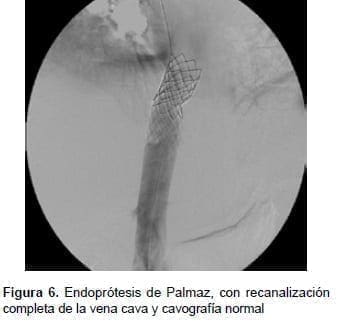

Se continuó colocando dos endoprótesis (stents) de Palmaz con balón montado de 24 mm de diámetro (Cordis™ – Johnson & Johnson).

La vena cava se recanalizó de manera completa y las venas suprahepáticas eran permeables (figura 6).